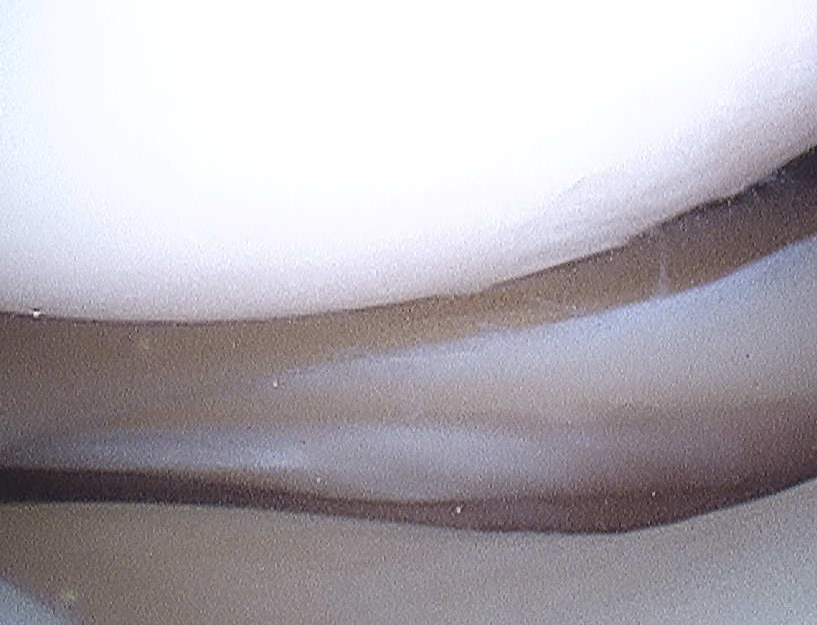

2 Bundles

1. Anterolateral

- most important

- double the size of the posteromedial

- tight in flexion

- try to reconstruct this bundle